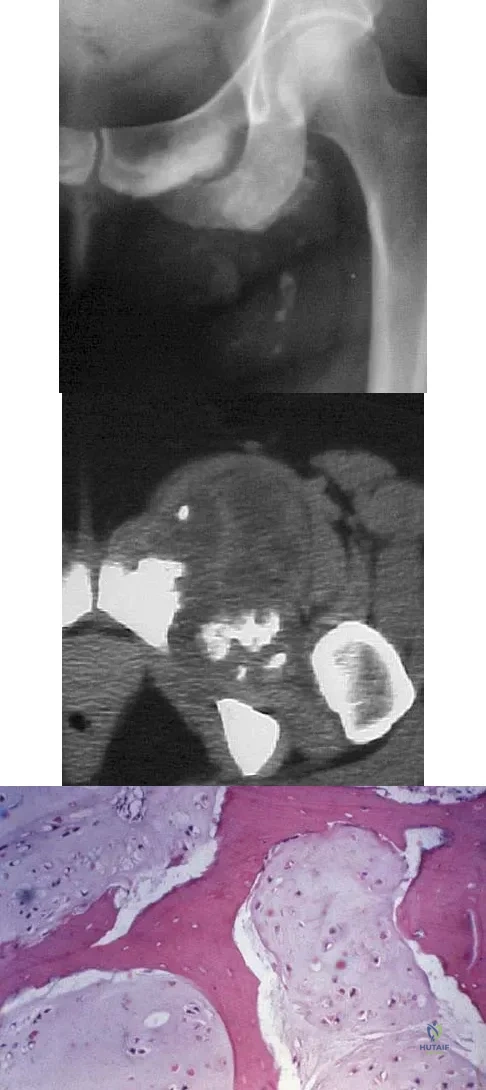

Question 77

A 40-year-old man has a painful mass on his anterior ankle joint with limited range of motion. A radiograph, MRI scan, a gross specimen, and a hematoxylin/eosin biopsy specimen are shown in Figures 5a through 5d. What is the most likely diagnosis?

Explanation